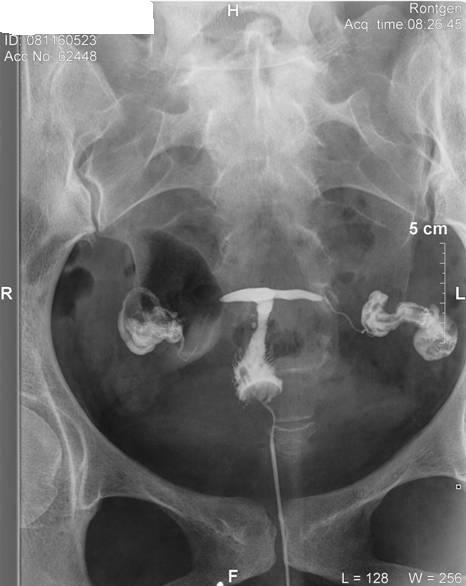

Hát hsg megvolt, nem volt egy rózsaszín leányálom mire felrakta a katéter, mert csak a második katéter ment be a helyére, és sokadik próbálkozásra!!!! :cry: Nem kívánom senkinek!!!!! De túl vagyok rajta, jobb mint a lapar!!!!!! :roll:

Szóval a helyzet az, hogy történt valami odabent, mert rettentő vékonyak lettek a vezetékek, kanyargósak, és a főnököm és az itteni nőgyógyi (aki felrakta a katétert) szerint hegesen gyógyultam régebbi gyulladásból. :cry: Szerinte ne is az inszemivel, hanem a lombikkal próbálkozzunk!!!!! :? :cry: Hát elkenődtem, mert nem erre számítottam, hiszen volt laparom, hsg-m eddig teljesen jó eredménnyel. :( Viszont megyek vissza a dokimhoz majd ha megjön, és megmondja a frankót!!!!! Hát ő azért már több ilyet látott, mint ez a nődoki!!!! :shock:

És a képes bizonyíték!!!!

Kép

én sem tudom, mit kell nézni a fotokon. de én is arra gondoltam, hogy ha kanyargos a petevezetö, akkor ott elakadhat a magzat, emiatt biztonságosabb lenne a lombik. ha babás leszel spontán, neked nem árt meg a röntgensugár? vagy nem közvetlen a sugárban dolghozol???